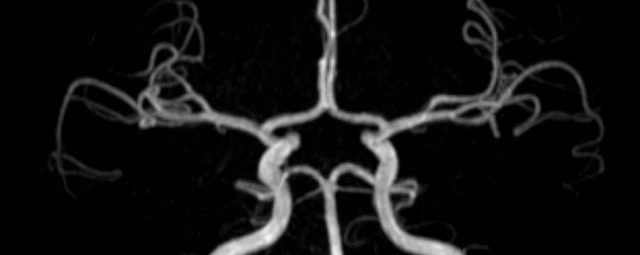

• intrakranielle Gefäße (Abklärung Verschluss, Stenose, Aneurysma)

• Halsgefäße zur Therapieplanung (z.B. Stent, Operation)

MR-Angiografie (MRA)

• MR-Angiografie ohne Kontrastmittel

• Time of Flight (TOF)-Angiographie

Je nach Fragestellung und Körperregion Gefäßdarstellung ohne Kontrastmittel bei Kontrastmittelunverträglichkeit oder terminaler Niereninsuffizienz möglich.